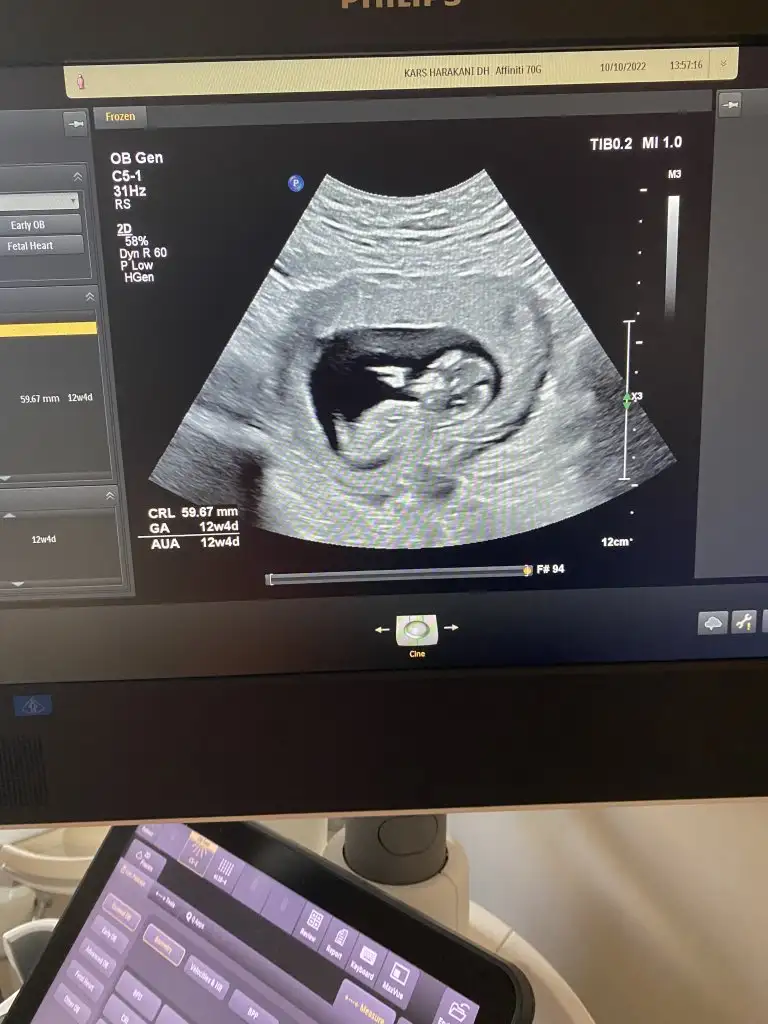

12 haftalık tahminde bulunabilir misiniz

• Screenshot_20221014-204033.webp

Screenshot_20221014-204033.webp

5,9 KB · Görüntüleme: 93